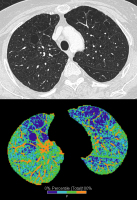

Computertomographie-COPD

Abbildung 1: Zentrilobuläres Emphysem bei einem 53 Jahre alten Patienten. Das Lungenemphysem ist durch fokale Areale mit verminderter Lungendichte gekennzeichnet (Pfeile).

Abbildung 2: Quantifizierung eines Lungenemphysems. Lungenareale mit Dichtewerten unter -950 Hounsfield Units (HU) werden als Emphysem definiert und entsprechend farbkodiert dargestellt.